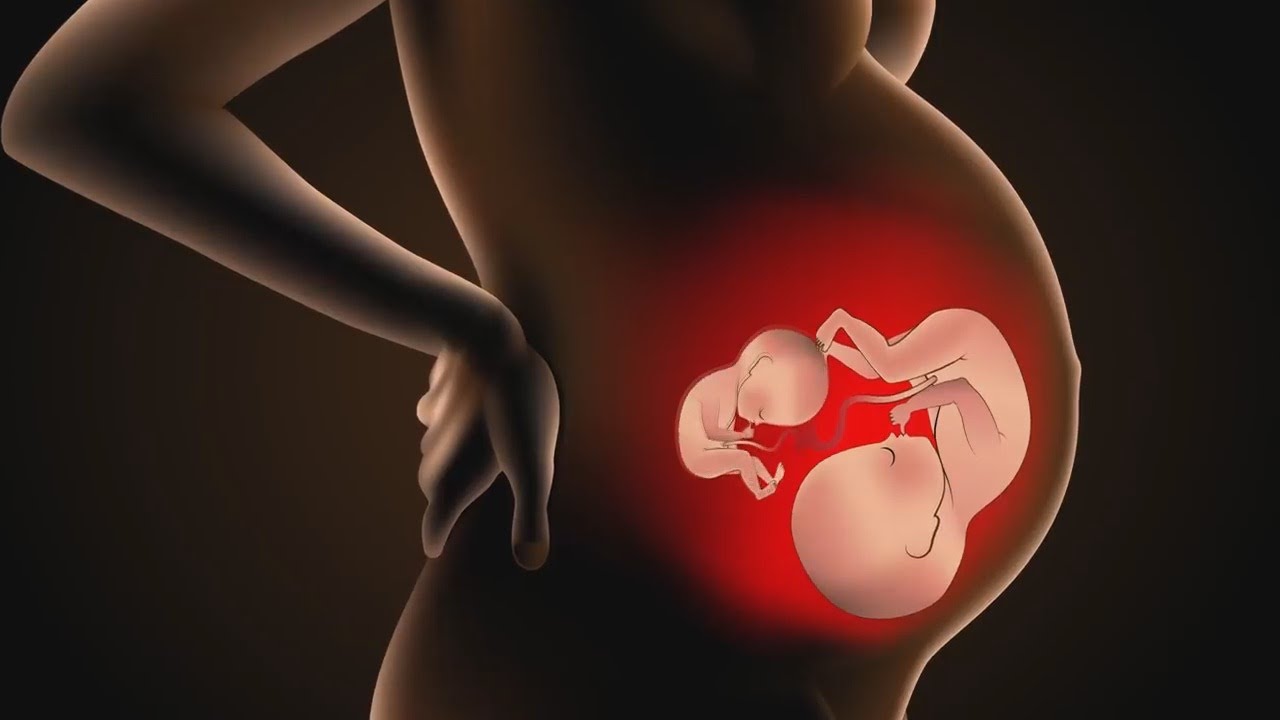

Фотография Плода В Животе

Фотография Плода В Животе 113 фотографий